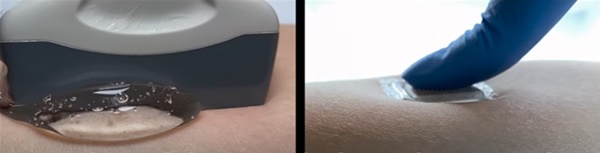

최대 장점은 작고 간단하다는 점이다. 훈련된 기술자가 환자 피부에 젤을 바르고 초음파 봉과 프로브(탐침)를 조작해 음파를 몸 안으로 유도할 필요도 없고 환자가 몸에 붙이기만 하면 영상을 얻을 수 있게 된다. 이미 자원자를 대상으로 적용해 본 결과 몸속 깊은 곳에 있는 기관의 고해상도 이미지를 실시간으로 볼 수 있었다. 또한 스티커는 자원자가 다양한 활동을 하는 동안 몸속 장기가 변화하는 모습을 또렷이 보여주었다.

기술자는 먼저 환자의 피부에 초음파를 전달하는 역할을 하는 액체 젤을 바른다. 그런 다음 탐침 또는 변환기를 젤에 대고 눌러서 음파를 몸 안으로 보내면 내부 구조물에서 메아리친(반향) 음파가 다시 탐침으로 보내진다. 여기서 반향된 신호가 시각적 이미지로 변환돼 모니터에 나타난다.

일부 병원에서는 오랜 시간 초음파 이미지 촬영을 해야 하는 환자들이 피곤하지 않도록 로봇 팔에 부착된 탐침을 제공해 변환기를 제자리에 고정시키기도 한다. 하지만 이 때도 액체 초음파 촬영용 젤은 시간이 지남에 따라 흘러내려 건조되면서 장시간 영상 촬영을 방해한다.

연구원들은 이 스티커를 건강한 자원자들의 목, 가슴, 복부, 팔을 포함한 몸의 다양한 부분에 붙이고 작동시켜 일련의 테스트를 했다. 그 결과 주요 혈관과 심장, 폐, 위 같은 몸속 더 깊은 곳에 있는 장기의 고해상도 이미지를 실시간으로 볼 수 있었다.

스티커들은 48시간 동안 시험 대상자들의 피부 아래 구조들의 선명한 이미지를 만들어 냈다. 스티커를 부착한 자원자는 앉기, 서기, 조깅, 자전거 타기, 역기에 이르기까지 다양한 활동을 실험실에서 수행했다. 스티커는 그동안 이들의 몸속에 있는 장기의 변화하는 모습을 포착해 보여 주었다.